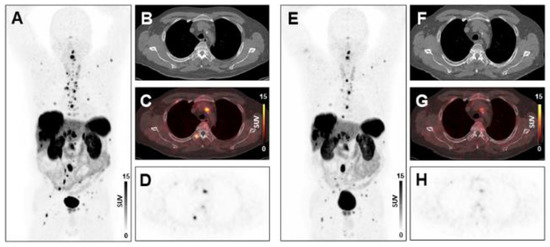

2.3. PET/CT Image Analysis

2.4. Assessment of Treatment Response and Clinical Endpoints